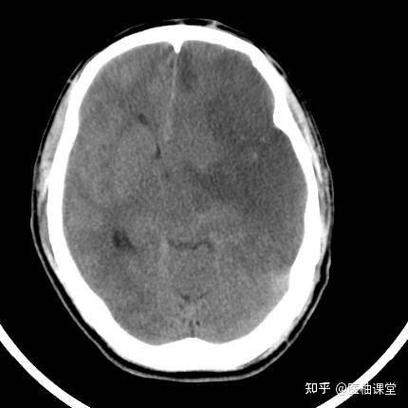

(图片来源网络,侵删)

脑CT在脑梗的急性期(发病后几小时内)主要作用是“排除”脑出血,而不是精确评估脑梗的“轻重”。 但随着时间的推移,CT在评估病情严重程度和范围方面的作用会越来越明显。

- 此时CT的主要任务是“鉴别诊断”。 医生做CT的首要目的是排除脑出血(脑出血在CT上会显示为高密度影,非常清晰),因为脑出血和脑梗的治疗方案完全相反,如果CT显示没有出血,医生才会高度怀疑是脑梗,并考虑后续的溶栓或取栓治疗。

在这个阶段,CT看“轻重”的能力有限,但并非完全没有线索: 经验丰富的放射科或临床医生可能会发现一些早期缺血征兆,这些征兆提示病情可能比较严重:

- 脑沟回模糊或消失: 缺血区域的脑沟会变浅、模糊。

- 脑实质密度轻度减低: 缺血区域的脑组织密度会比周围正常组织稍微低一点点,但非常不明显。

- 大脑中动脉高密度征: 在大脑中动脉走行的区域,看到一条高密度的“线条”,这可能是该动脉内有血栓形成的迹象,常常提示大血管闭塞,病情较重。

在发病6小时内,CT主要用于排除脑出血,早期缺血征兆提示可能为大血管梗死,但无法精确判断梗死的范围和最终损伤程度。